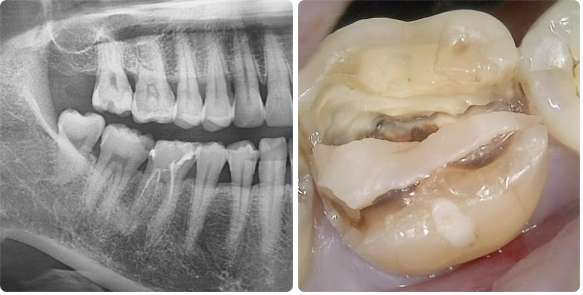

우선 임시 보철물을 장착한 뒤 약 한 달가량 경과를 지켜보았고,

일상적인 사용에 큰 불편이 없어 최종적으로 크라운치료를 진행했습니다.

그 결과 치아 기능을 안정적으로 회복할 수 있었습니다.